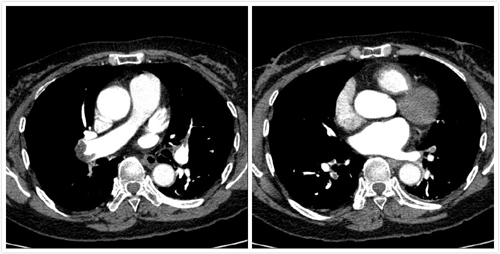

患者,女性,62岁,曾从事油漆工工作,工作有长时间站立、下蹲特点。因活动后胸闷、气短、呼吸困难3日,加重1日主诉入院,入院后经心内二科张晓锋主任、吕强副主任医师仔细分析患者症状及心电图、血气分析后,肺动脉CTA检查迅速明确诊断,确定该患者介入手术适应证,预计会有较好的疗效。在充分与患者及家属沟通,同意肺动脉造影及抽栓、碎栓、药物溶栓手术治疗。吕强副主任医师、张晓锋主任医师、潘立栋医师、邵玉玲主管护师、车晓伟技师组成的手术小组在经历一个多小时紧张而有条不紊的操作后,顺利完成了肺动脉血栓抽栓、碎栓、药物溶栓抢救。患者术后取得了立竿见影的效果,胸闷、气短、呼吸困难明显减轻,次日复查动脉血气分析氧分压明显改善,目前患者恢复良好。

△ 溶栓前

△ 溶栓后